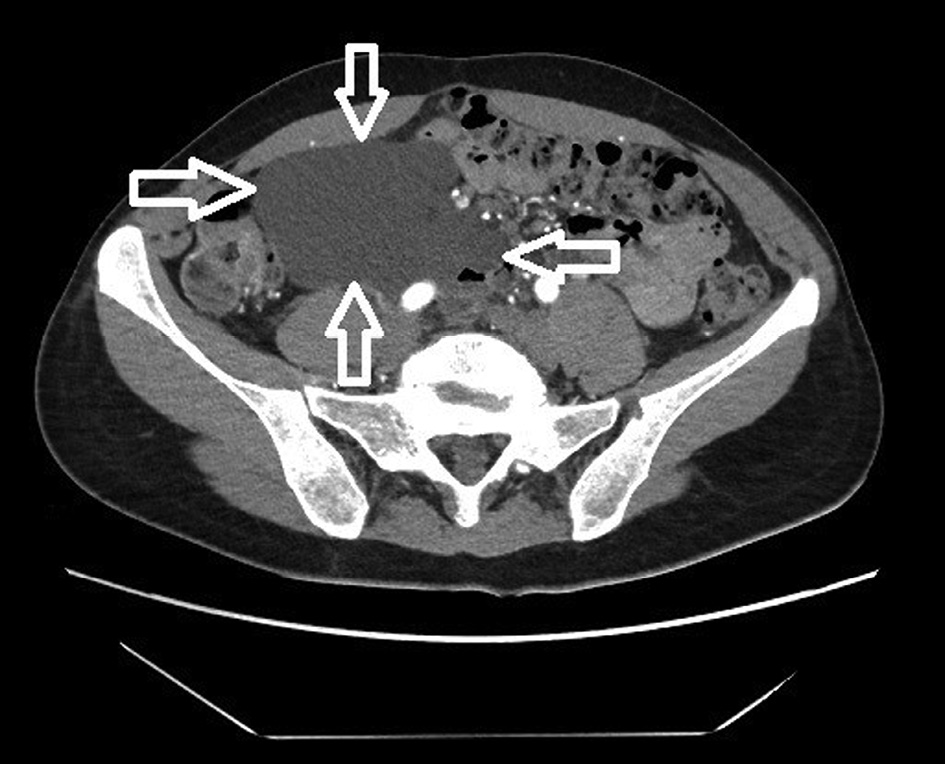

The 42-year-old woman sought medical attention for periodically occurring moderately severe pain in the lower abdomen. Intermittent lower abdominal pain occurred 2 years ago for the first time. She was investigated in the emergency department a few times. The pain gradually increased over the time. Physical examination revealed that the patient was well and no physical changes were identified. CT scan revealed a clearly defined, hypodensic, cystic, without clear solid components mass, about 11 cm × 10 cm × 6,5 cm, ventrally reaching the right side of abdomen wall, dorsally contacting abdominal aorta, inferior vena cava and right common iliac artery, caudally lying on the ileocolic artery and vein (Fig. 1 and Fig. 2). The mass extended from pancreatic head and superior mesenteric vein near ileum to right iliac area along the ileocolic artery and vein. Lymphangioma of the ileum mesentery was suspected. Also, an atypical anatomy of the celiac trunk was detected.